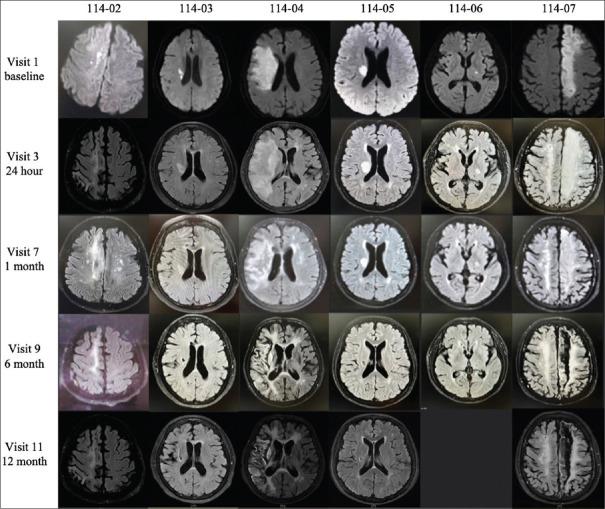

MATERIALS AND METHODS

We conducted a 12-month, open-label, and single-center, phase I trial of hUCB treatment in AIS patients at the age of 45-80 years, with magnetic resonance imaging evidence of acute infarction in the internal carotid artery supplied territory and the National Institute of Health Stroke Scale (NIHSS) score between 6 and 18. Eligible participants received a single-dose IV infusion of hUCB followed by the two doses of mannitol infusion within 9 days after the onset of stroke symptoms. The primary endpoint was the incidence of adverse events (AEs) and the secondary endpoints were the changes in NIHSS, Barthel index (BI), and Berg Balance Scale (BBS) scores.

我们开展了一项为期12个月、开放标签、单中心的I期试验,纳入年龄在45至80岁之间的AIS患者,这些患者经磁共振成像证实颈内动脉供血区域存在急性梗死,且美国国立卫生研究院卒中量表(NIHSS)评分在6至18分之间。符合条件的参与者接受单次静脉输注hUCB,随后在卒中症状发作后9天内输注两剂甘露醇。主要终点是不良事件(AE)的发生率,次要终点是NIHSS、Barthel指数(BI)和Berg平衡量表(BBS)评分的变化。